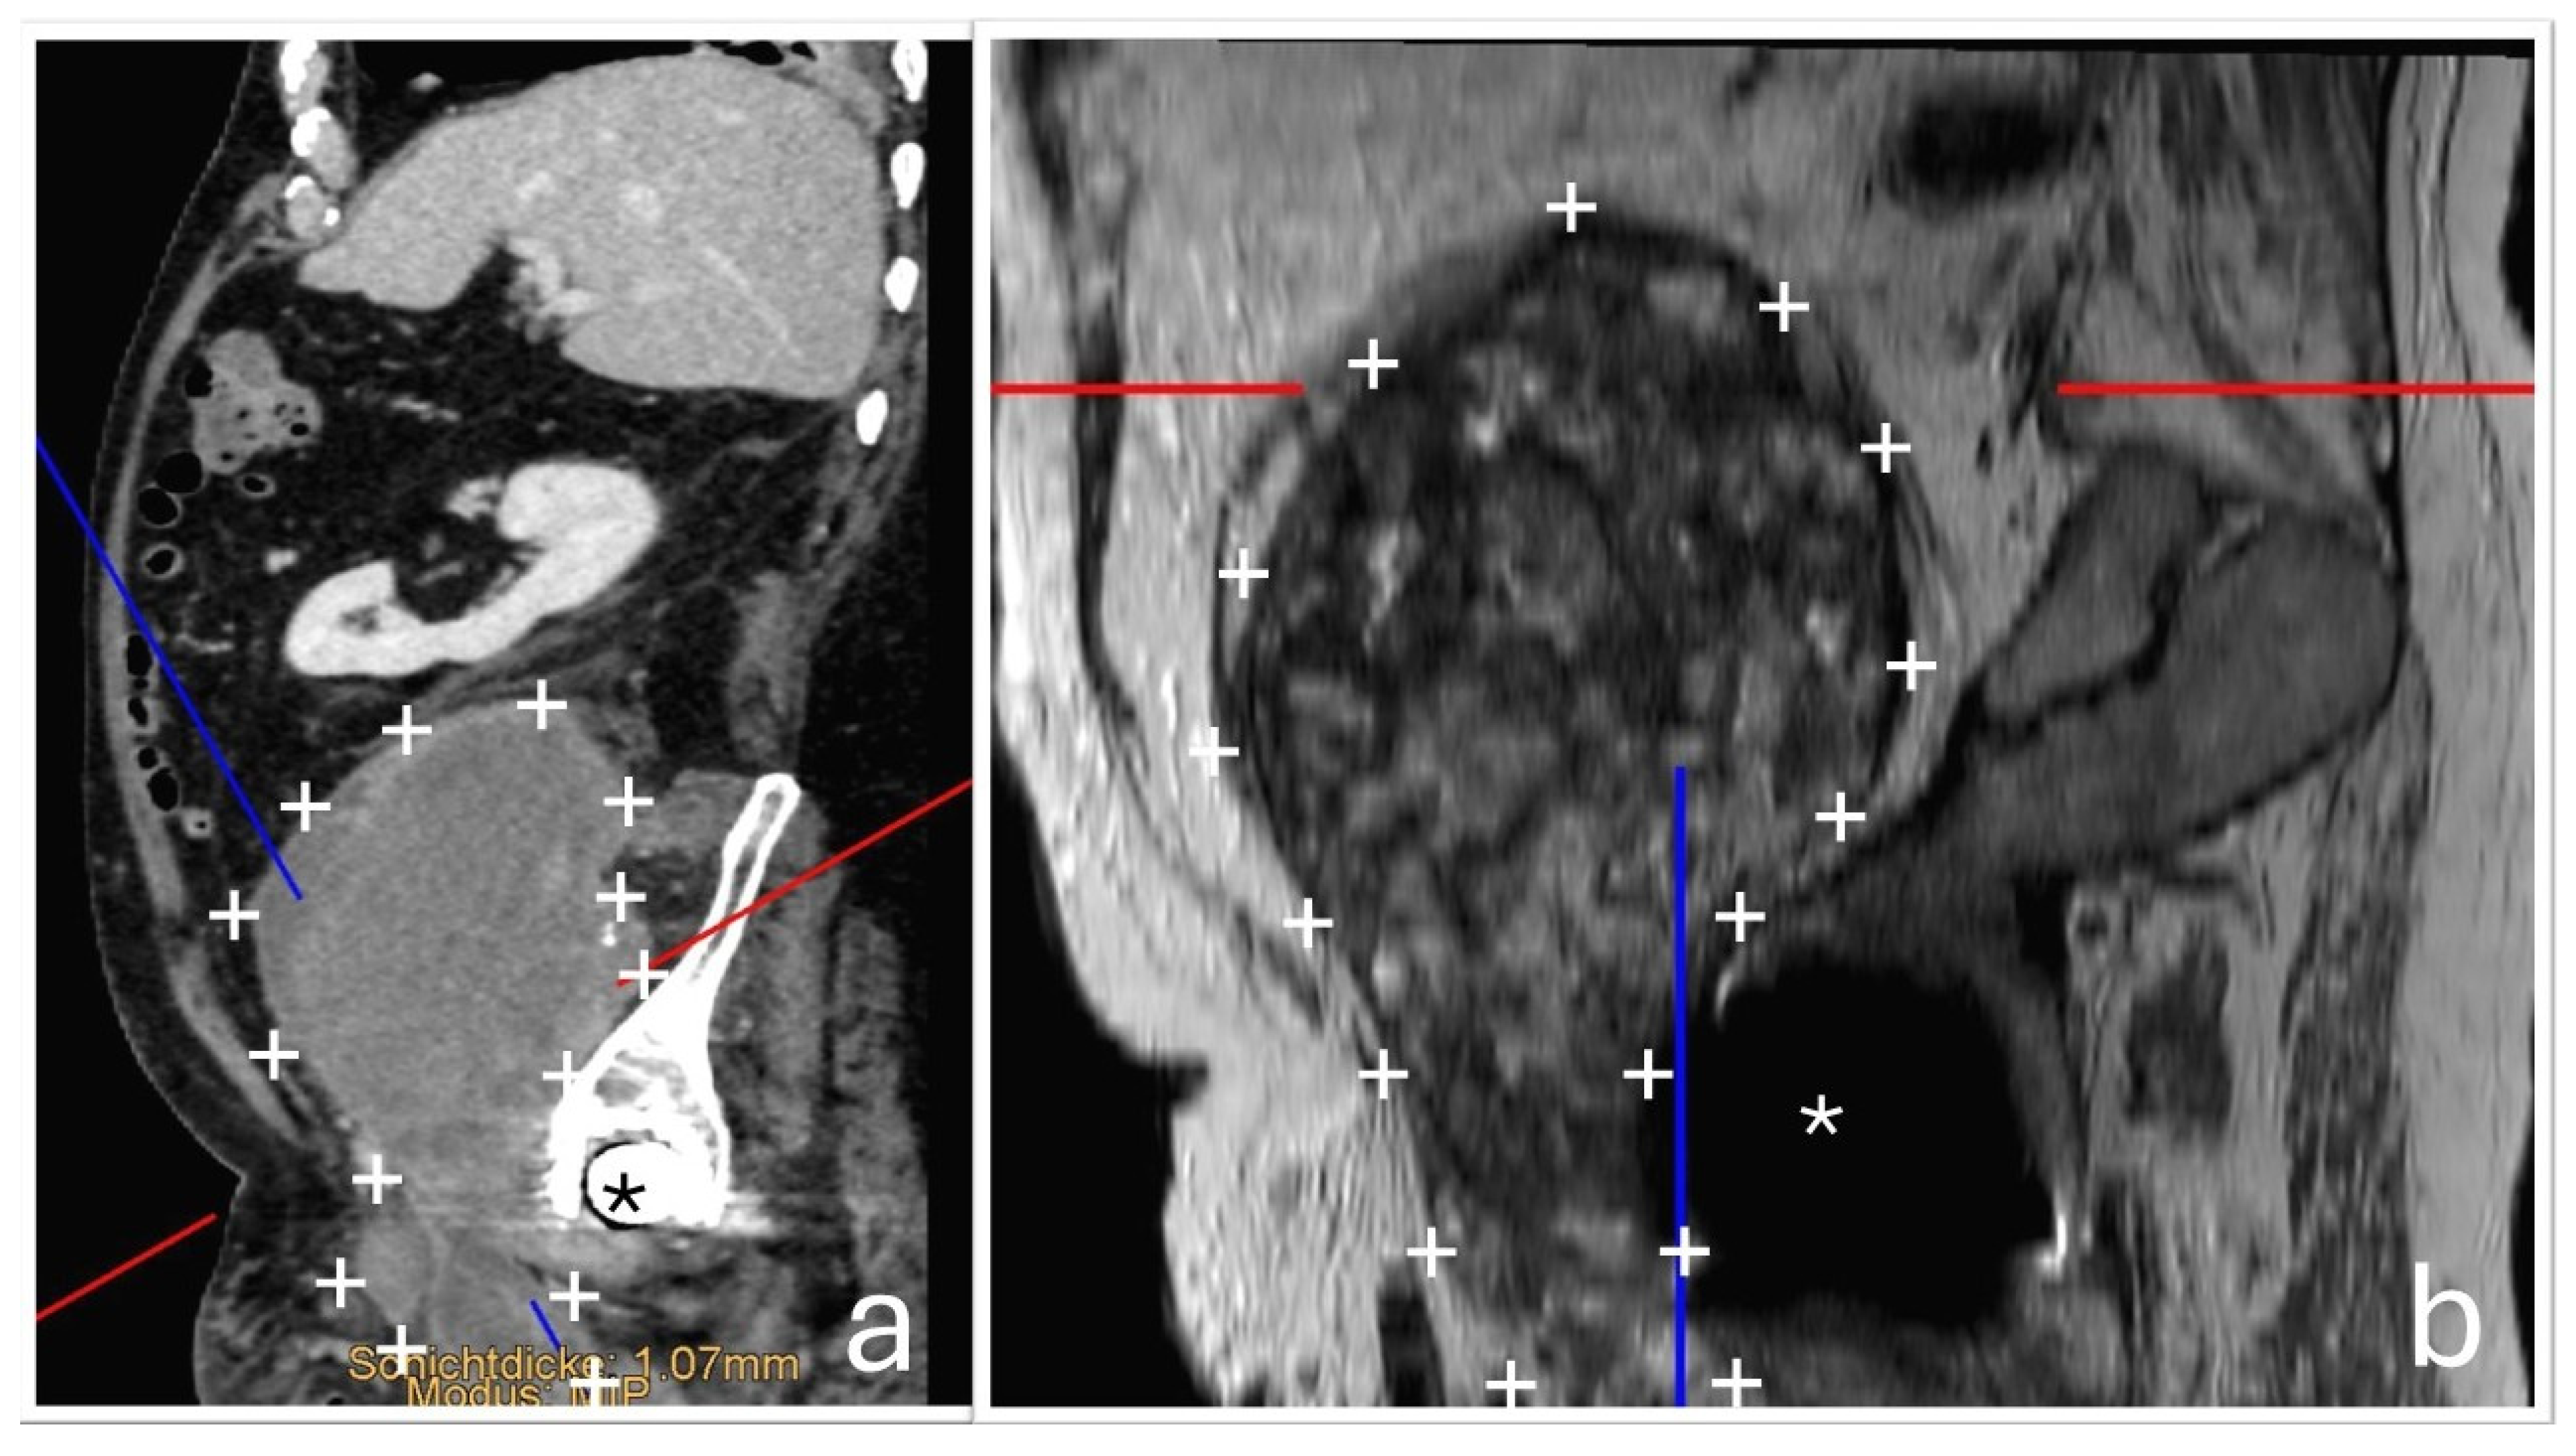

The tissue was macroscopically trimmed and representatively embedded in paraffin. Sections were stained with hematoxylin and eosin and examined by light microscopy. Histological analysis showed a mixed chronic and active inflammatory response with metal and polyethylene wear particles, necrosis, and hemorrhage. The surrounding fibrotic capsule exhibited a lymphohistiocytic and florid inflammation. Findings were consistent with an organizing, encapsulated hematoma, without evidence of neoplastic infiltrates (Figure 6).

Figure 6. (a) Hematoxylin and eosin (H&E) staining at 200× magnification. It demonstrates a mixed inflammatory response. Numerous neutrophilic granulocytes and areas of erythrocyte extravasation are visible. Macrophages are prominent, including hemosiderin-laden macrophages (identified by brown pigment, →) and macrophages containing metal debris (black pigment, ∆). Additionally, there is extensive capillary proliferation (*), indicative of a chronic inflammatory process. (b) H&E staining at 400× magnification. It reveals a granulomatous inflammatory reaction with increased numbers of macrophages, predominantly with an epithelioid phenotype (←), and so-called ‘ghost particles’ (○): Polyethylene appears optically empty in H&E staining and presents as narrow, spindle-shaped or roundish voids, often without coloration (as polyethylene is not stainable).